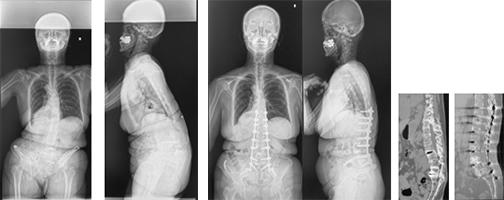

前方後方矯正固定術

背骨が大きく変形している場合や再手術の際に前方手術と後方手術を両方行って、せぼねの矯正と固定を行います。1日で両方の手術を行う場合と2日間に分けて手術を行う場合があります。大人の患者様では3週間程度で場合によってはリハビリテーション病院へ転院をして頂き、さらにリハビリテーションを行います。

-

成人期遺残特発性側弯症に対する前・後方矯正固定術 -

成人脊柱変形に対するLIFを併用した前方後方矯正固定術